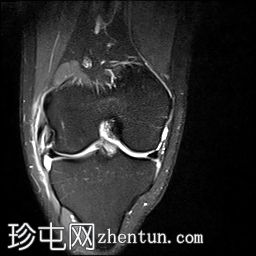

冠状位PD序列

脂肪抑制序列

前交叉韧带(ACL)完全断裂,PDFS和T2加权像显示韧带中部纤维信号增高,残余纤维下垂于胫骨平台,冠状位可见空切迹征。

外侧副韧带也存在水肿,纤维断裂,提示为III级损伤。